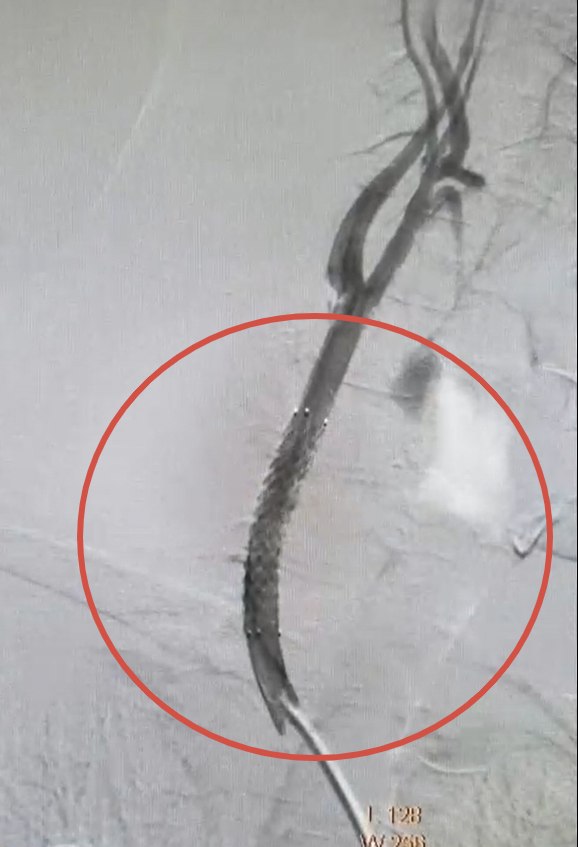

Спасти жизнь помогла современная эндоваскулярная операция. Хирурги Валерий Казанов и Алексей Подтуркин через небольшой прокол в бедренной артерии доставили к поражённому участку стент-графт — специальную трубку с металлическим каркасом, которая укрепила сосуд и предотвратила разрыв.

- Ювелирную работу сделали возможной благодаря новому ангиографическому комплексу с 3D-визуализацией высочайшего качества, — отметила врио министра здравоохранения региона Екатерина Письменная.